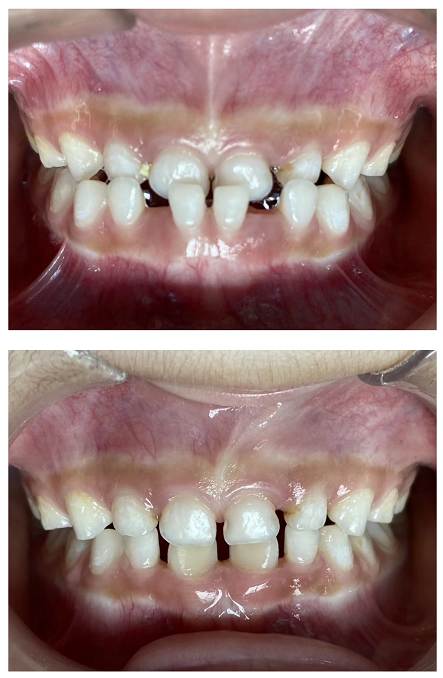

口腔科主要开展牙体牙髓治疗、牙周治疗、牙齿美容、齿槽外科治疗、义齿修复、种植牙、正畸治疗、儿童口腔治疗、口腔粘膜病的中西医结合治疗等多个业务项目。其中特色的种植牙业务及正畸治疗、牙体牙髓治疗项目,都是区内领先。